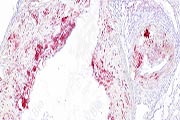

陕西依科生物技术服务有限公司致力于生物科研试剂的研发、销售及相关技术服务。从事的领域包括石蜡包埋、切片、HE染色、冰冻切片、各种特殊染色、免疫染色、Tunel染色和其他相关病理技术服务。同时,公司还建立了独立实验室,开展Real-time PCR和Western blot等分子生物学实验及其他相关检测。公司拥有经验丰富的销售人员、专业技术人员和病理学专家可提供高质量的检测服务,为您递呈合理的病理学图片和满足杂志要求的实验结果。欢迎新老客户来电垂询。...

免疫组化实验中如何最大限度地降低组织非特异性染色?1.缩短一抗/二抗孵育时间、稀释抗体来控制。这是最...

1.由于组织中部分抗原在甲醛或多聚甲醛固定过程中,发生了蛋白之间交联及醛基的封闭作用,从而失去抗原性...

1.单克隆和多克隆抗体的选择。由一种克隆产生的特异性抗体叫做单克隆抗体。单克隆抗体能目标明确地与单一...